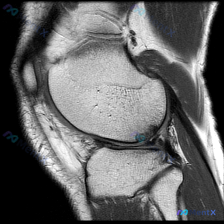

这是一张膝关节MRI矢状位T1加权像,临床提示怀疑存在软骨异常,需要我们读片分析。

- 序列与定位确认:这是标准的膝关节矢状位T1加权像,左侧为前,右侧为后,上方是股骨远端,下方是胫骨近端;T1序列特点是脂肪呈高信号,液体、韧带、半月板呈低信号,符合序列特点。

- 骨骼骨髓:股骨远端、髌骨、胫骨近端骨髓信号均匀,没有异常低信号灶,骨皮质完整,没有骨折或破坏

- 关节软骨:股骨髁和胫骨平台软骨厚度正常,没有明显局灶信号增高或大面积缺损

- 半月板:形态连续,呈均匀低信号,没有明确高信号撕裂线

- 交叉韧带:后交叉韧带形态信号正常,前交叉韧带在此层面未显示全程,可见部分无异常

- 肌腱:髌腱、股四头肌腱结构正常,无信号增高或肿胀

- 关节腔与软组织:无明显异常积液,周围软组织层次清晰,无水肿或占位

读片结论:此单层面T1加权像上,膝关节所有结构都没有发现明确的形态和信号异常。